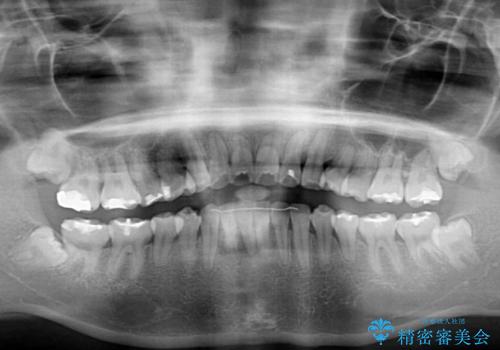

- 上下前歯を部分矯正したところ出っ歯になってしまったとのことで来院された患者様です。

上下左右第一小臼歯4本を抜歯して、積極的に口元を引っ込めるよう、ワイヤー装置にて矯正治療を行うこととしました。